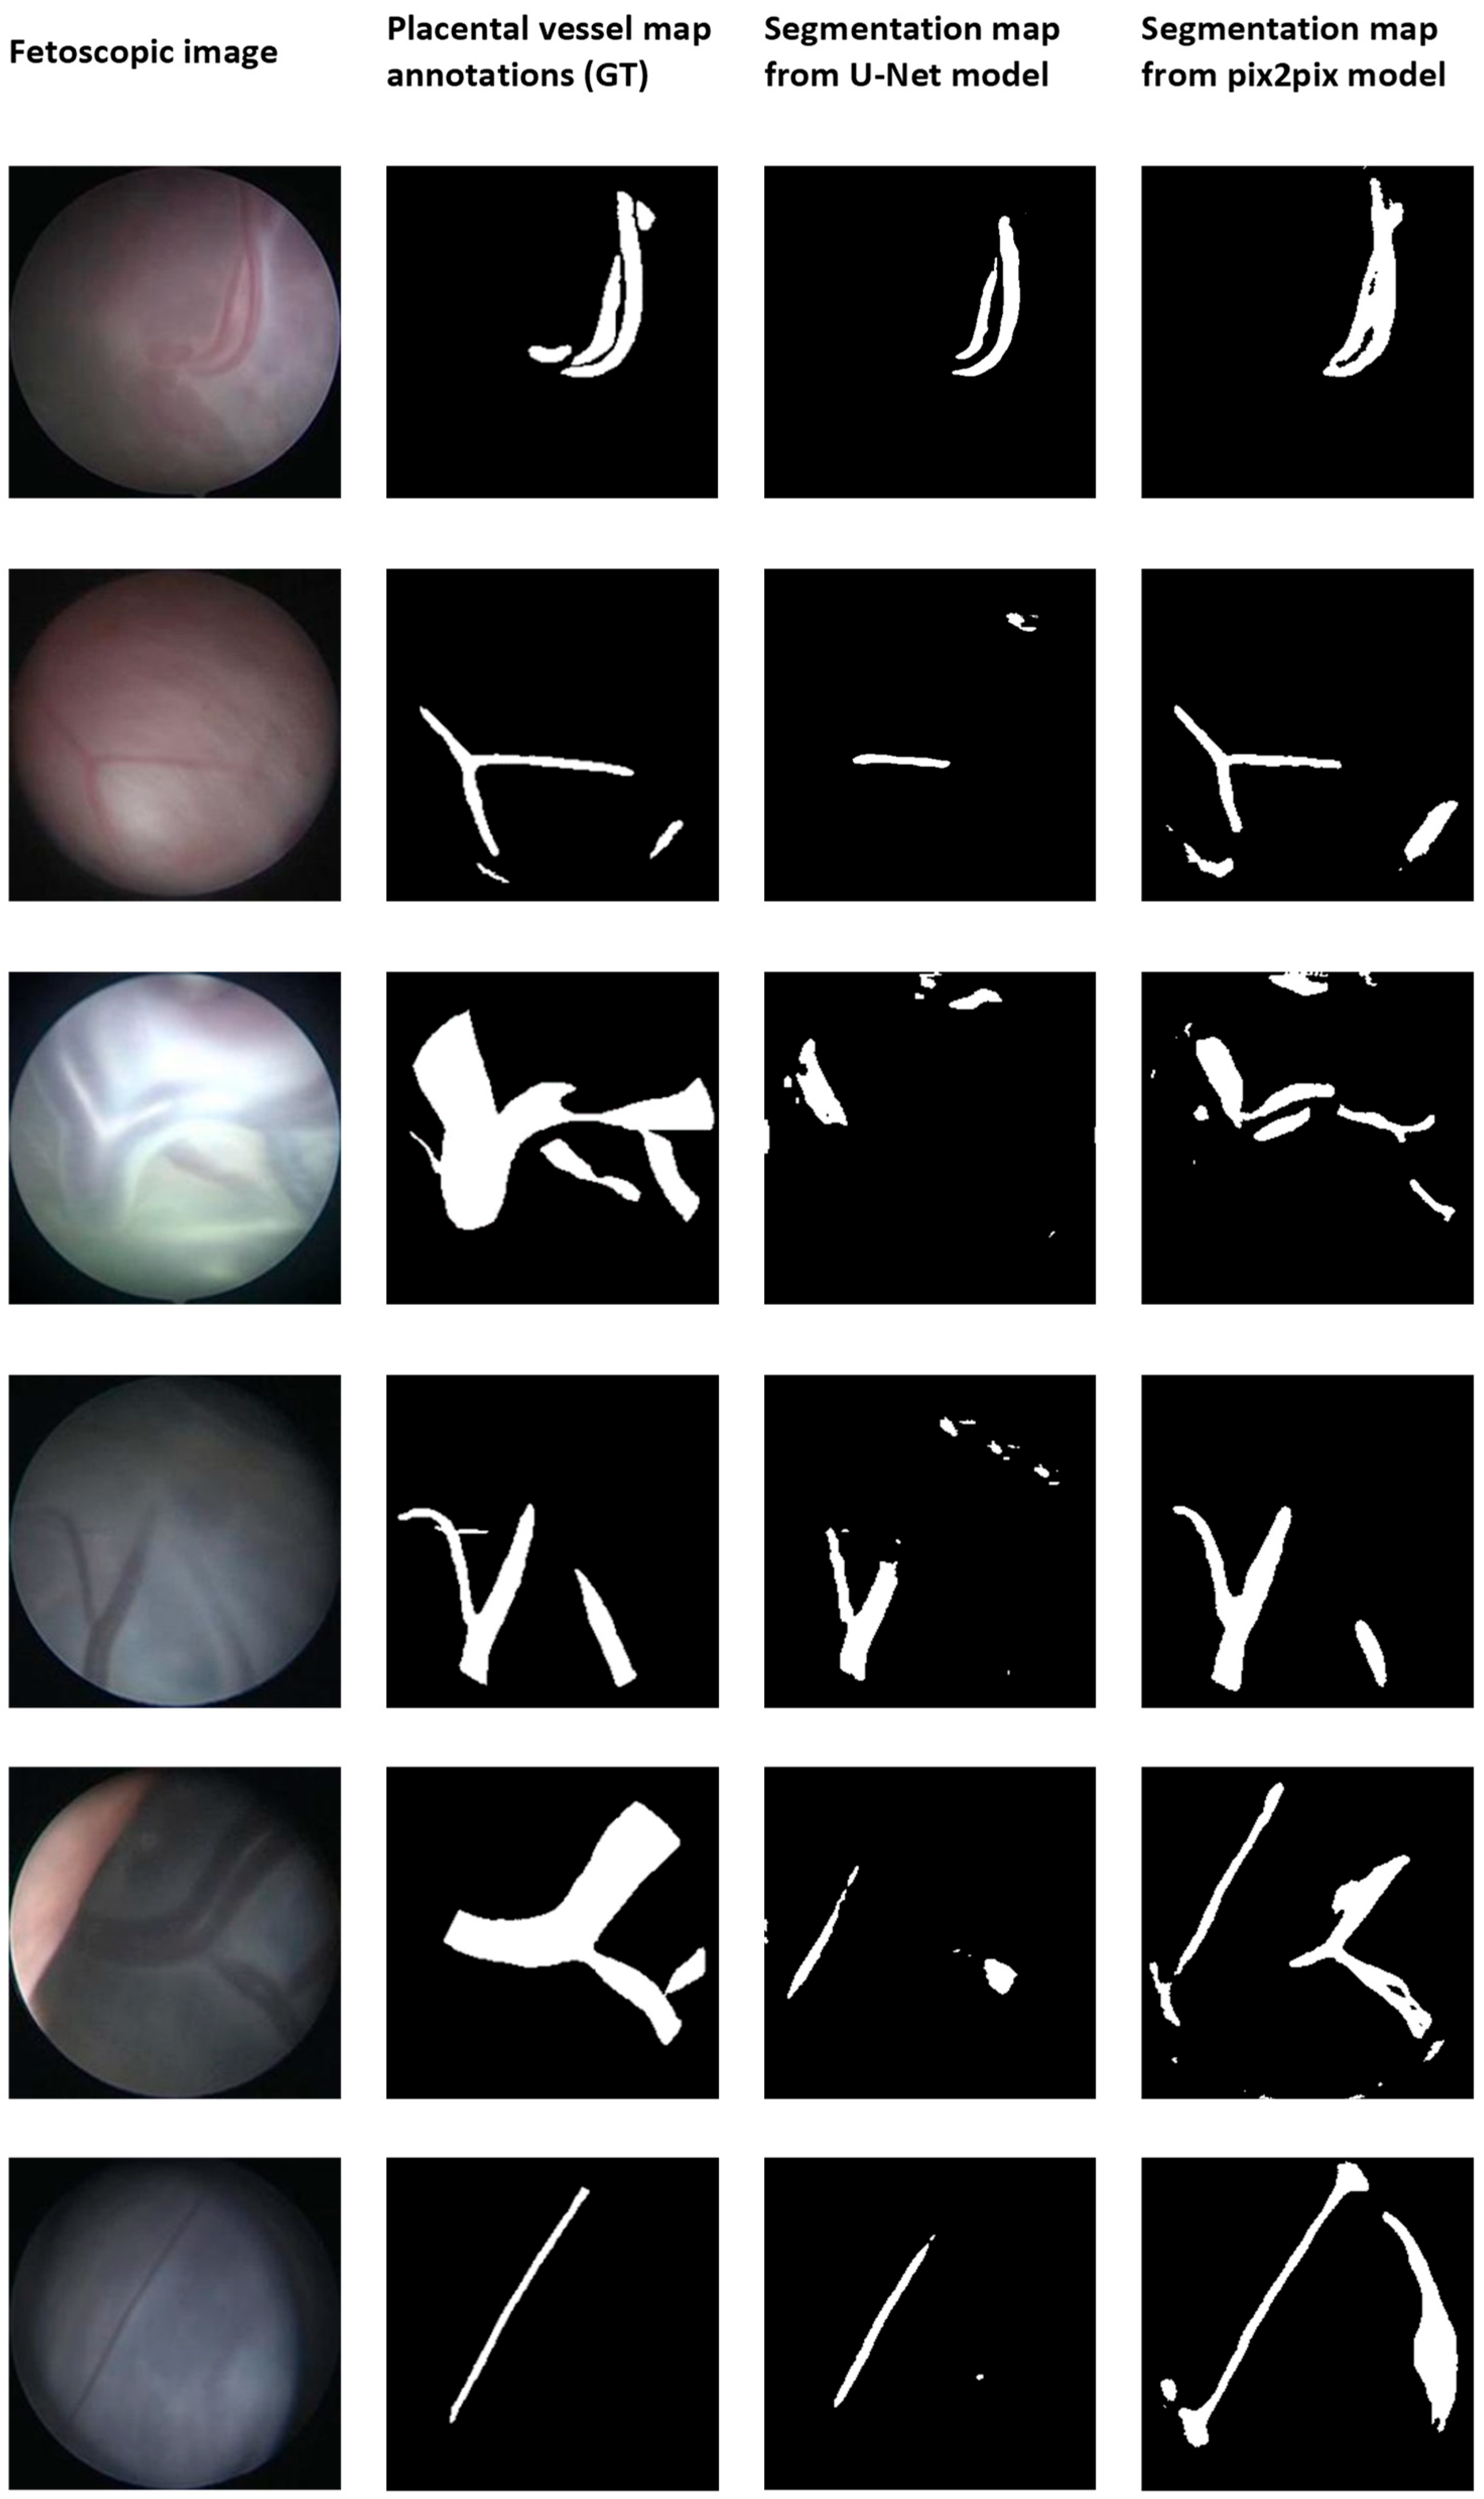

3. Results